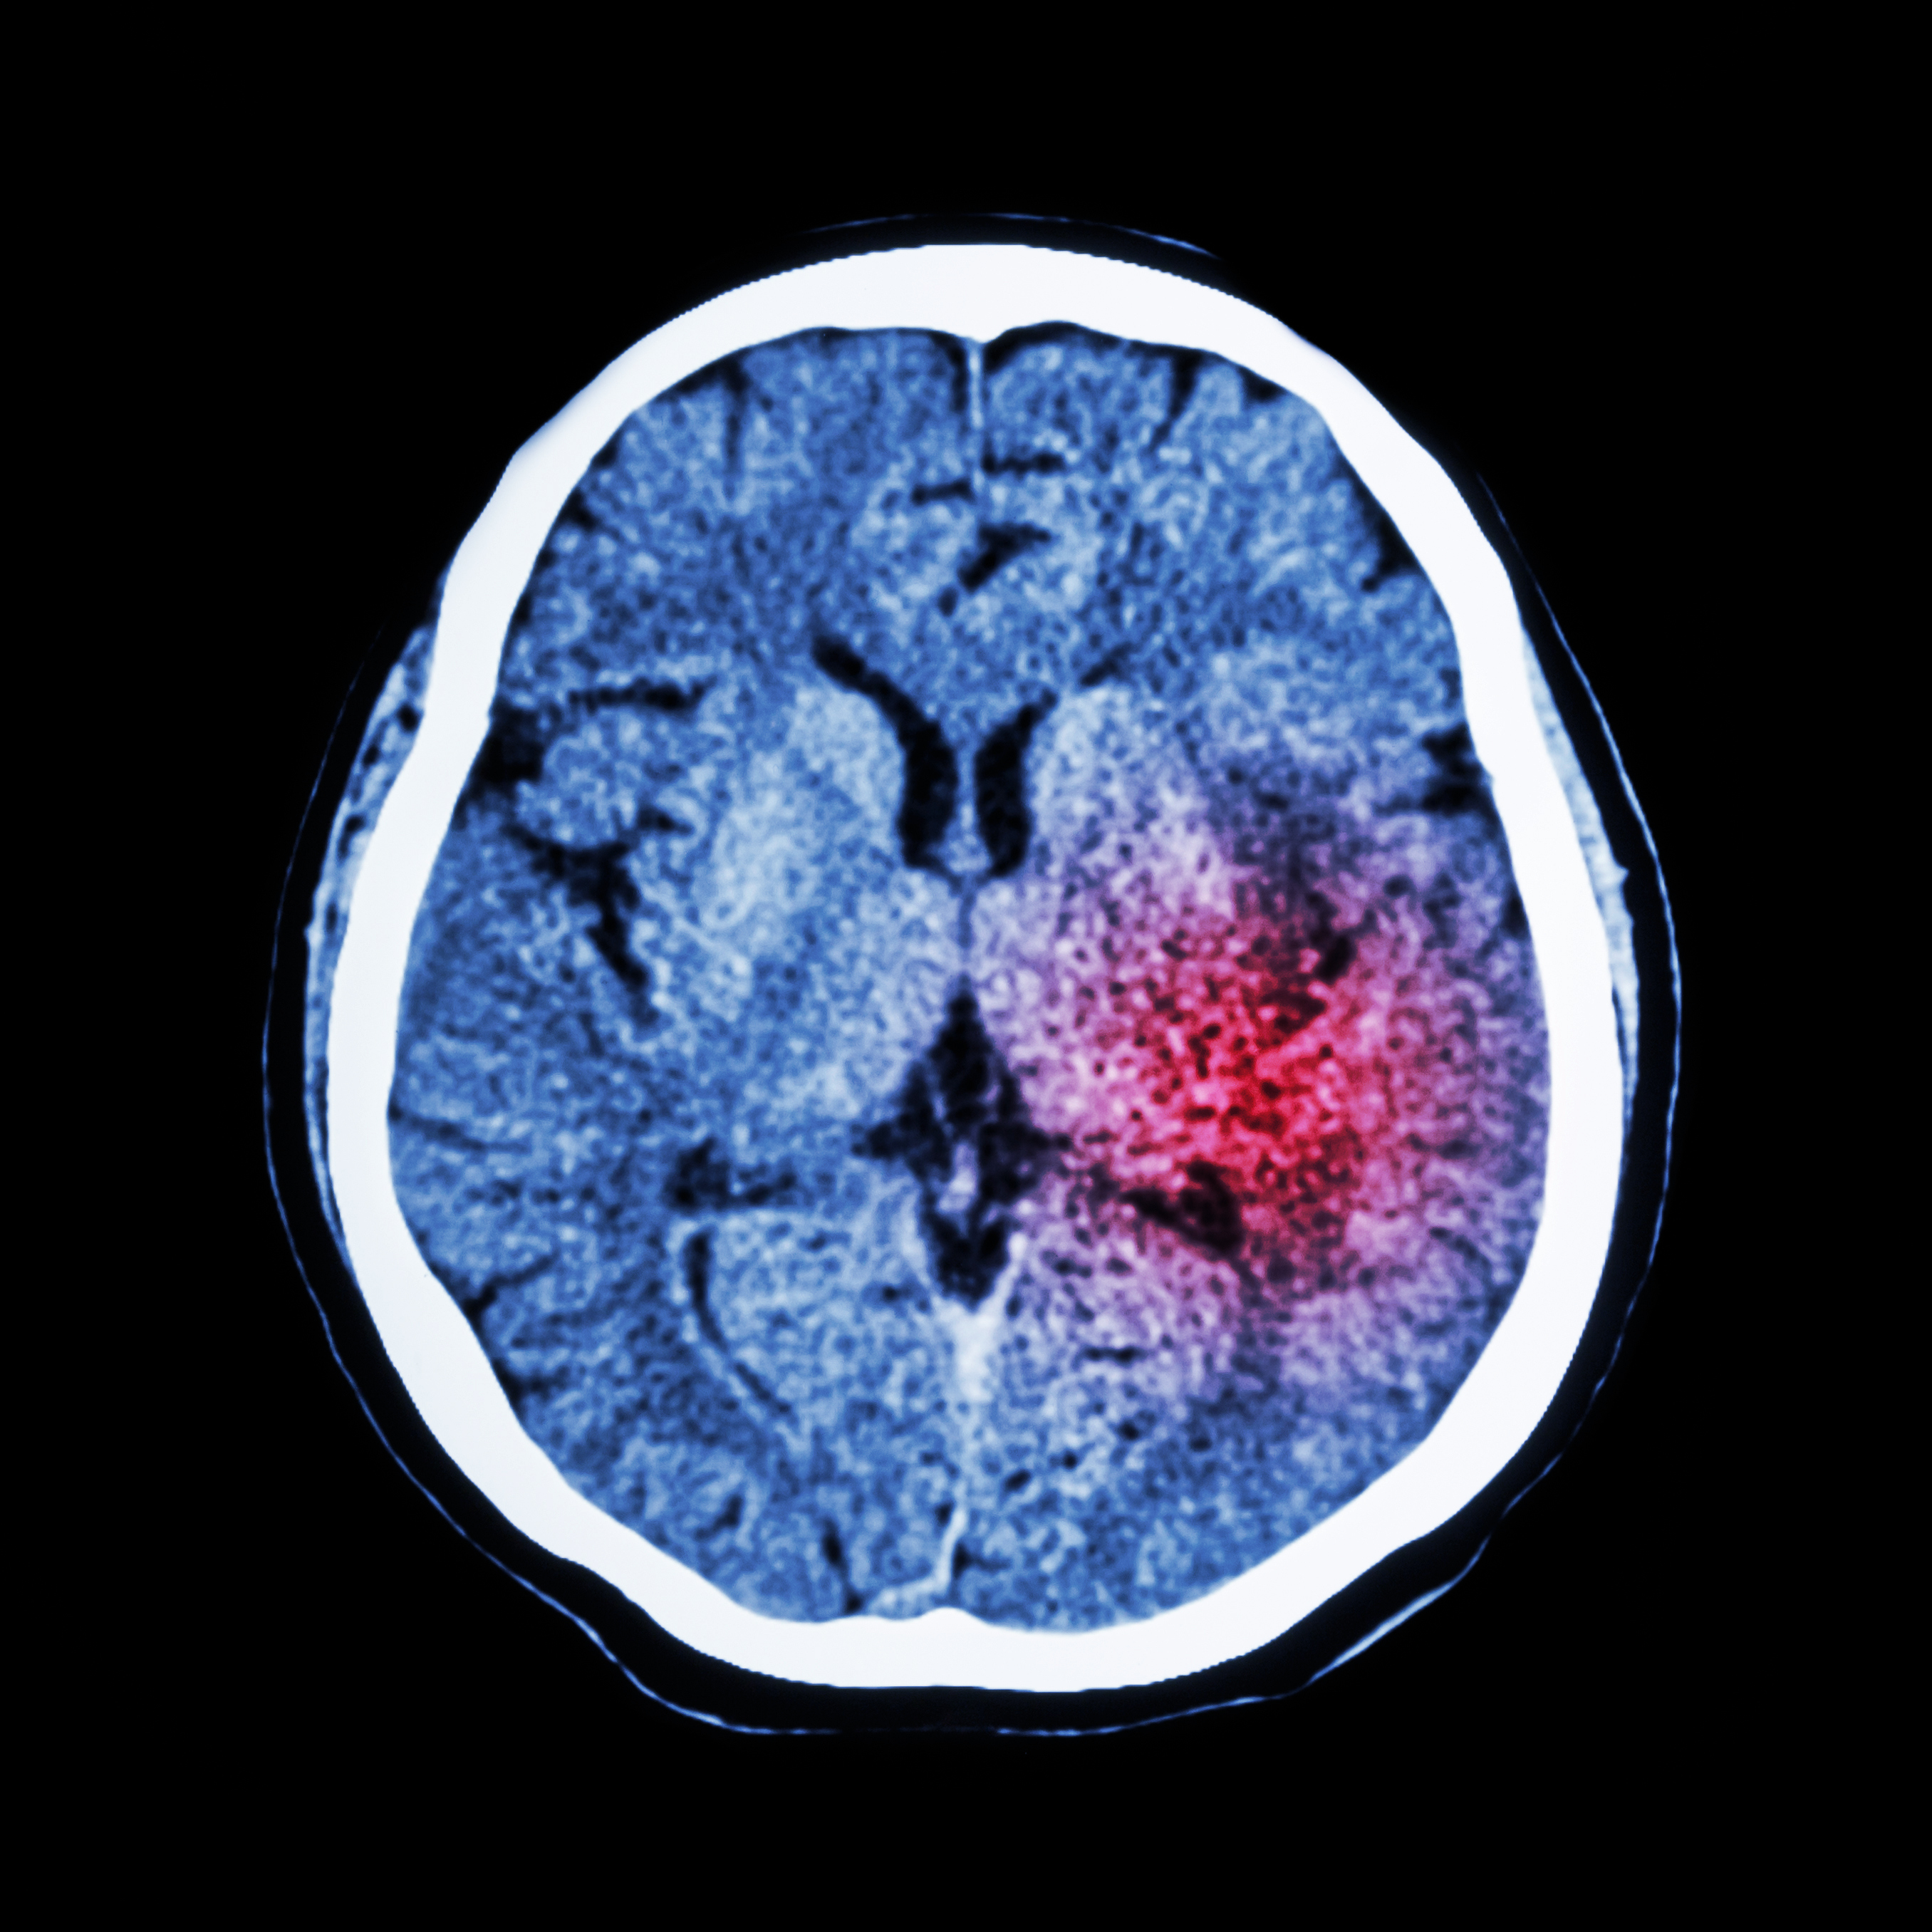

En studie fra britisk allmennpraksis viser at den primærforebyggende behandling av hjerneslag er for dårlig.

Lipidsenkende, antikoagulerende og blodtrykksenkende legemidler kan forebygge hjerneslag hos mange pasienter. I en studie fra britisk allmennpraksis med flere enn 26 000 pasienter med hjerneslag i perioden 2009 – 13 ble forskrivningen av slike legemidler forut for hjerneslaget kartlagt (1). Av dem som fikk sitt første hjerneslag eller transitoriske iskemiske anfall i denne perio-den, sto bare omtrent halvparten på slike legemidler. Til tross for at det var klinisk indikasjon for behandling hadde 49 % ikke fått lipidsenkende legemidler, 52 % hadde ikke fått antikoagulerende legemidler og 25 % ikke blodtrykkssenkende legemidler. Forfatterne beregnet at ca. 12 000 tilfeller av hjerneslag og transitoriske iskemiske anfall årlig kan forebygges i Storbritannia med bedre primærprofylaktisk behandling.